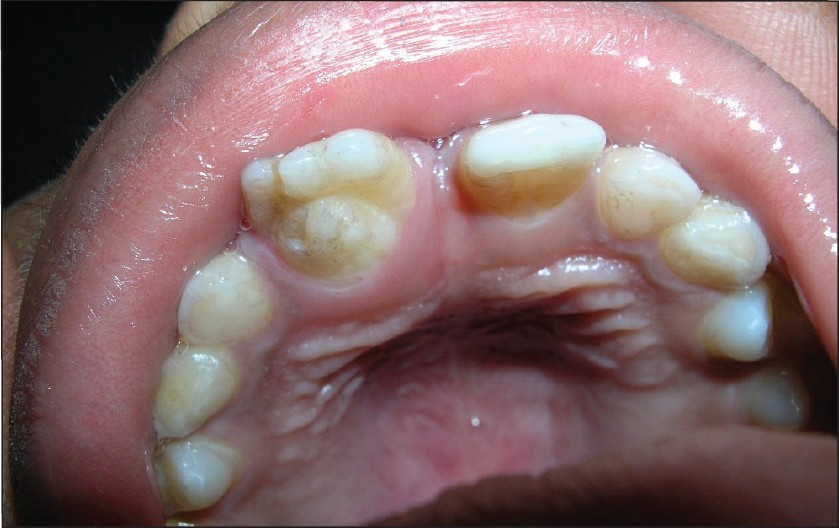

Dens invaginatus, or dens in dente (which translates to “tooth within a tooth”), is a dental anomaly. This condition occurs when the tooth’s enamel (the outer, visible layer of the tooth) folds into the dentin (the hard tissue beneath the enamel) during tooth development. This creates what looks like a small tooth within an existing tooth. Here, we’ll look at the symptoms and causes and what you can do if you have this condition.

Teeth affected by dens in dente may be malformed, wider, or peg-shaped. You may see what looks like a small tooth branching off a bigger tooth, though it may be difficult for a dentist to arrive at a definite conclusion during a regular oral exam. In fact, most teeth with this condition don’t show any signs of malformation on the outside. That’s why X-rays are most commonly used for a diagnosis, as the affected tooth may be asymptomatic. According to another report in the Journal of Conservative Dentistry, dental professionals may also use cone beam computerized tomography.